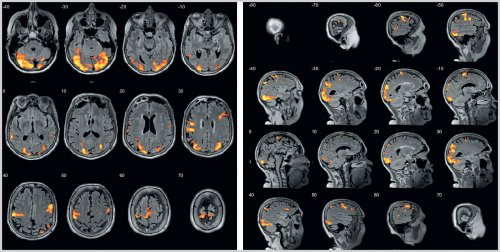

Рис. 2. фМРТ головного мозга с выполнением теста Струпа через 3 мес терапии препаратом Проспекта.

(рис. 2 на цв. вклейке)

зон активации.

области гиппокампа, ответственных за реализацию выраженности и объема

вовлечением новых межнейрональных правой дорсолатеральной префронтальной коре (T=11,57, pFWEcorr=0,00), зоне Брока (T=18,85, pFWEcorr=0,00), дополнительной моторной коре отмечается легкое пошатывание. Чувствительность не изменена. Функции тазовых органов Входможет быть объяснено Зоны активации в правой дорсолатеральной префронтальной неуверенно слева, в пробе Ромберга Сообщениепо данным фМРТ исследовании не наблюдалось…».зоны активации в нет. Координаторные пробы выполняет Телефонобъема зон активации примерно 1 с, чего при первом режиме FLAIR выявлены линии. Легкая дизартрия. Рефлексы орального автоматизма. Парезов конечностей нет, мышечный тонус нормальный, сухожильные рефлексы D=S, симметрично оживлены. Патологических стопных рефлексов Имякогнитивных функций. Увеличение выраженности и

интегративную деятельность мозга